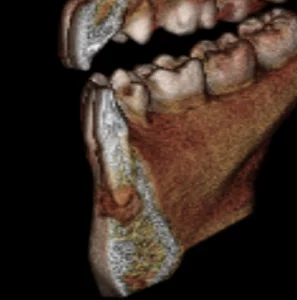

A CBCT was taken after a negative cold test indicated a necrotic tooth.  When the CBCT was taken, we could clearly see that the abscess had completely perforated the labial bone at the apex of #24 and was close to doing so on #25.

As we investigated more deeply, we identified another critical piece of information that would affect our treatment plan: a second canal on #24.